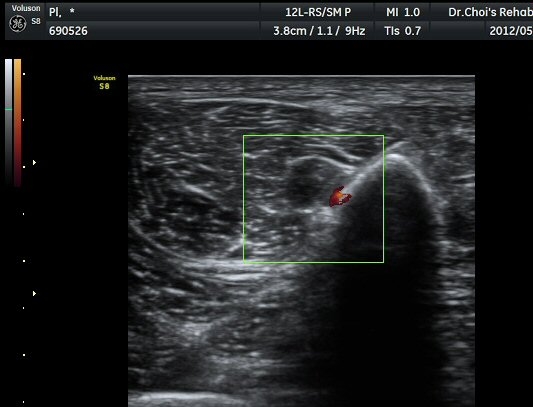

ŽÃËÀÚ¸¦ ´õ ¾Æ·¡·Î À̵¿ÇÏ´Ï Ãµºñ°ñ½Å°æÀÌ Àú¿¡ÄÚ µÕ±Ù µ¢¾î¸®·Î °üÂûµÇ´Ù°¡ ´Ù½Ã Á¤»óÀûÀÎ ¸ð½ÀÀ¸·Î °üÂûµÈ´Ù(±×¸² 7, 8).

µ¢¾î¸® Á¾´Ü¸é°Ë»ç¿¡¼­ µ¢¾î¸®ÀÇ ±ÙÀ§ºÎ°¡ ½Å°æ°ú ¿¬°áµÇ¾î ÀÖÀ½À» °üÂûÇÒ ¼ö ÀÖ´Ù(±×¸² 9).